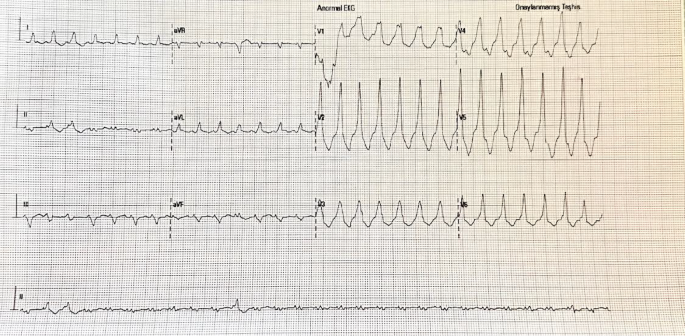

在这份技术报告中,我们介绍了一位因装有双金属人工瓣膜而采用经心室入路进行VT消融的患者。该患者为69岁男性,左心室射血分数为25%,被诊断为非缺血性心肌病。他接受了心脏再同步化治疗(CRT-D),并且对药物治疗无效的适当心内除颤器电击也无反应。患者因诊断为VT风暴被送入导管实验室。图中显示了患者VT期间的12导联心电图(图1)。

为了降低动脉损伤的风险,在通过左前降支(LAD)的间隔分支时,通过插入左主干冠状动脉(LMCA)开口的6F Judkins导管注入不透明造影剂来进行可视化观察(视频2,图2)。在间隔映射过程中,当以100毫米/秒的频率进行起搏时,在V1导联观察到W形波形(图3